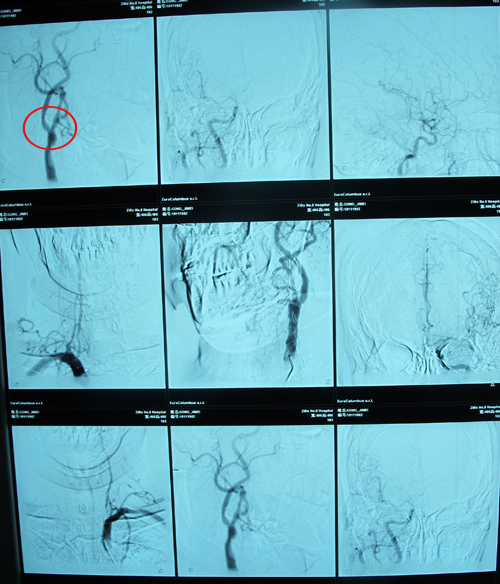

全脑血管造影:右颈总动脉及分叉处70%狭窄,右颈内动脉起始部两处狭窄分别为50%。颈内C4、C6段分别狭窄40%、65%。右大脑中动脉M1段狭窄50%。右大脑前动脉较纤细,示发育不佳。左颈总动脉多发粥样硬化斑块,至边缘不清,左颈内动脉起始处狭窄30%,左侧大脑前动脉、中动脉未见异常。